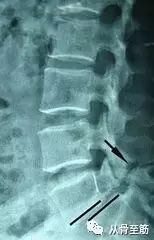

? ? CT在显示骨性结构上有优势,可清楚显示小关节增生肥厚、椎管及侧隐窝狭窄、椎间盘突出部位、程度,有无钙化及神经根受压情况等。